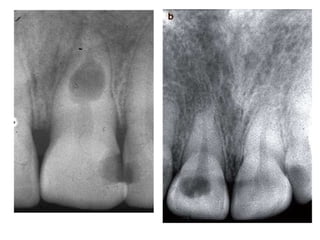

Radiographical features:

In initial stages,periapical granuloma show widening

of the

periodontal ligament space of the tooth.

Fully developed lesions usually produce a well

defined

radiolucent area of varying size which appears to be

in continuity with the root apex.

Long standing periapical granuloma may show

varying

degrees of root resorption.

Apical Periodontal Cyst

• RADIOGRAPHIC FEATURES:

• Radiolucency – round/ ovoid with a narrow

opaque margin which is continuous with

lamina dura.

• In long standing cyst bone resorption of

affected teeth & occasional resorption of adj.

teeth may be seen.

Radiographical features: In initialstages,periapical granuloma show widening of the periodontal ligament space of the tooth. Fully developed lesions usually produce a well defined radiolucent area of varying size which appears to be in continuity with the root apex. Long standing periapical granuloma may show varying degrees of root resorption.

Apical Periodontal Cyst •RADIOGRAPHIC FEATURES: • Radiolucency – round/ ovoid with a narrow opaque margin which is continuous with lamina dura. • In long standing cyst bone resorption of affected teeth & occasional resorption of adj. teeth may be seen.